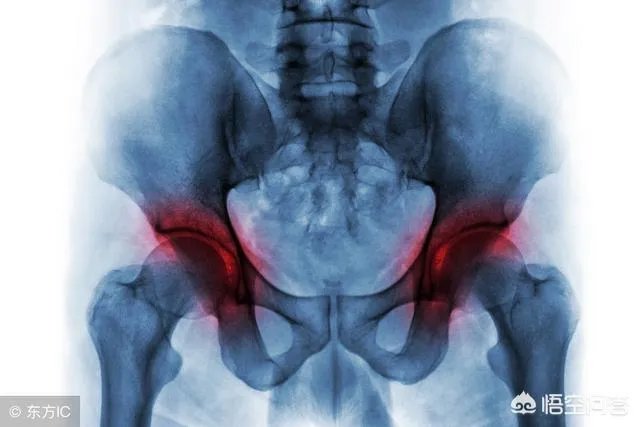

作为一名骨外科医生,临床工作上还真的遇到不少这样的病人,下面就结合个人实际讲讲遇到的运气比较好的病人吧!主任曾经说过,见过一个长期喝酒导致一侧股骨头坏死的患者,20年前就因为疼痛过来看病的,当时主任还是个年轻大夫,因为没有做关节置换的指征,于是就给病人做了保守治疗,并同时跟患者说:如果后期出现疼痛加剧,股骨头坏死加重塌陷的话,可能需要行关节置换手术.......

然而20年过去了,每一次这个病人来复查的时候,股骨头坏死情况真的一次比一次差,病人逐渐出现股骨头坏死塌陷,因为单看片子来说,已经具有手术的适应症了,主任多次劝该患者做手术。

但患者目前至今仍未行关节置换手术,因为他股骨头虽然坏死,但老人家不痛,关节活动也没有明显受限,能走能睡,但他一早就把酒戒了!单看片子来说,是已经有明显的手术指征了,但病人没有明显症状、不影响关节活动,不希望做手术,做完有可能比现在还痛!!

这个幸运的老人家是个特例,但这个病人告诉我们:长期喝酒容易导致股骨头坏死,早期戒酒可以避免股骨头的进一步坏死!对于股骨头坏死的病人,也都不是全部需要做关节置换手术!患者生活质量不明显受限,能多挨一年是一年!写这个病例的目的在于强调对于特殊病人、特殊疾病需要特殊对待,而不是提倡大家有病在家里扛着,对于疾病的诊治,听医生的还是没错的!